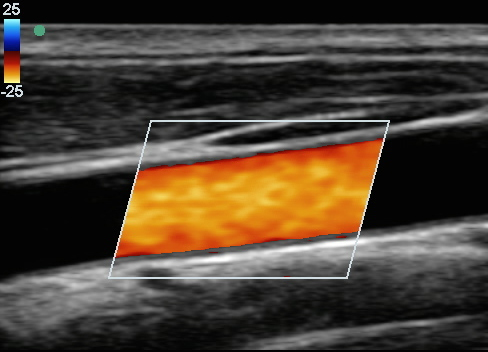

Farbbild 2: Karotis – Arteria carotis communis (ACC)